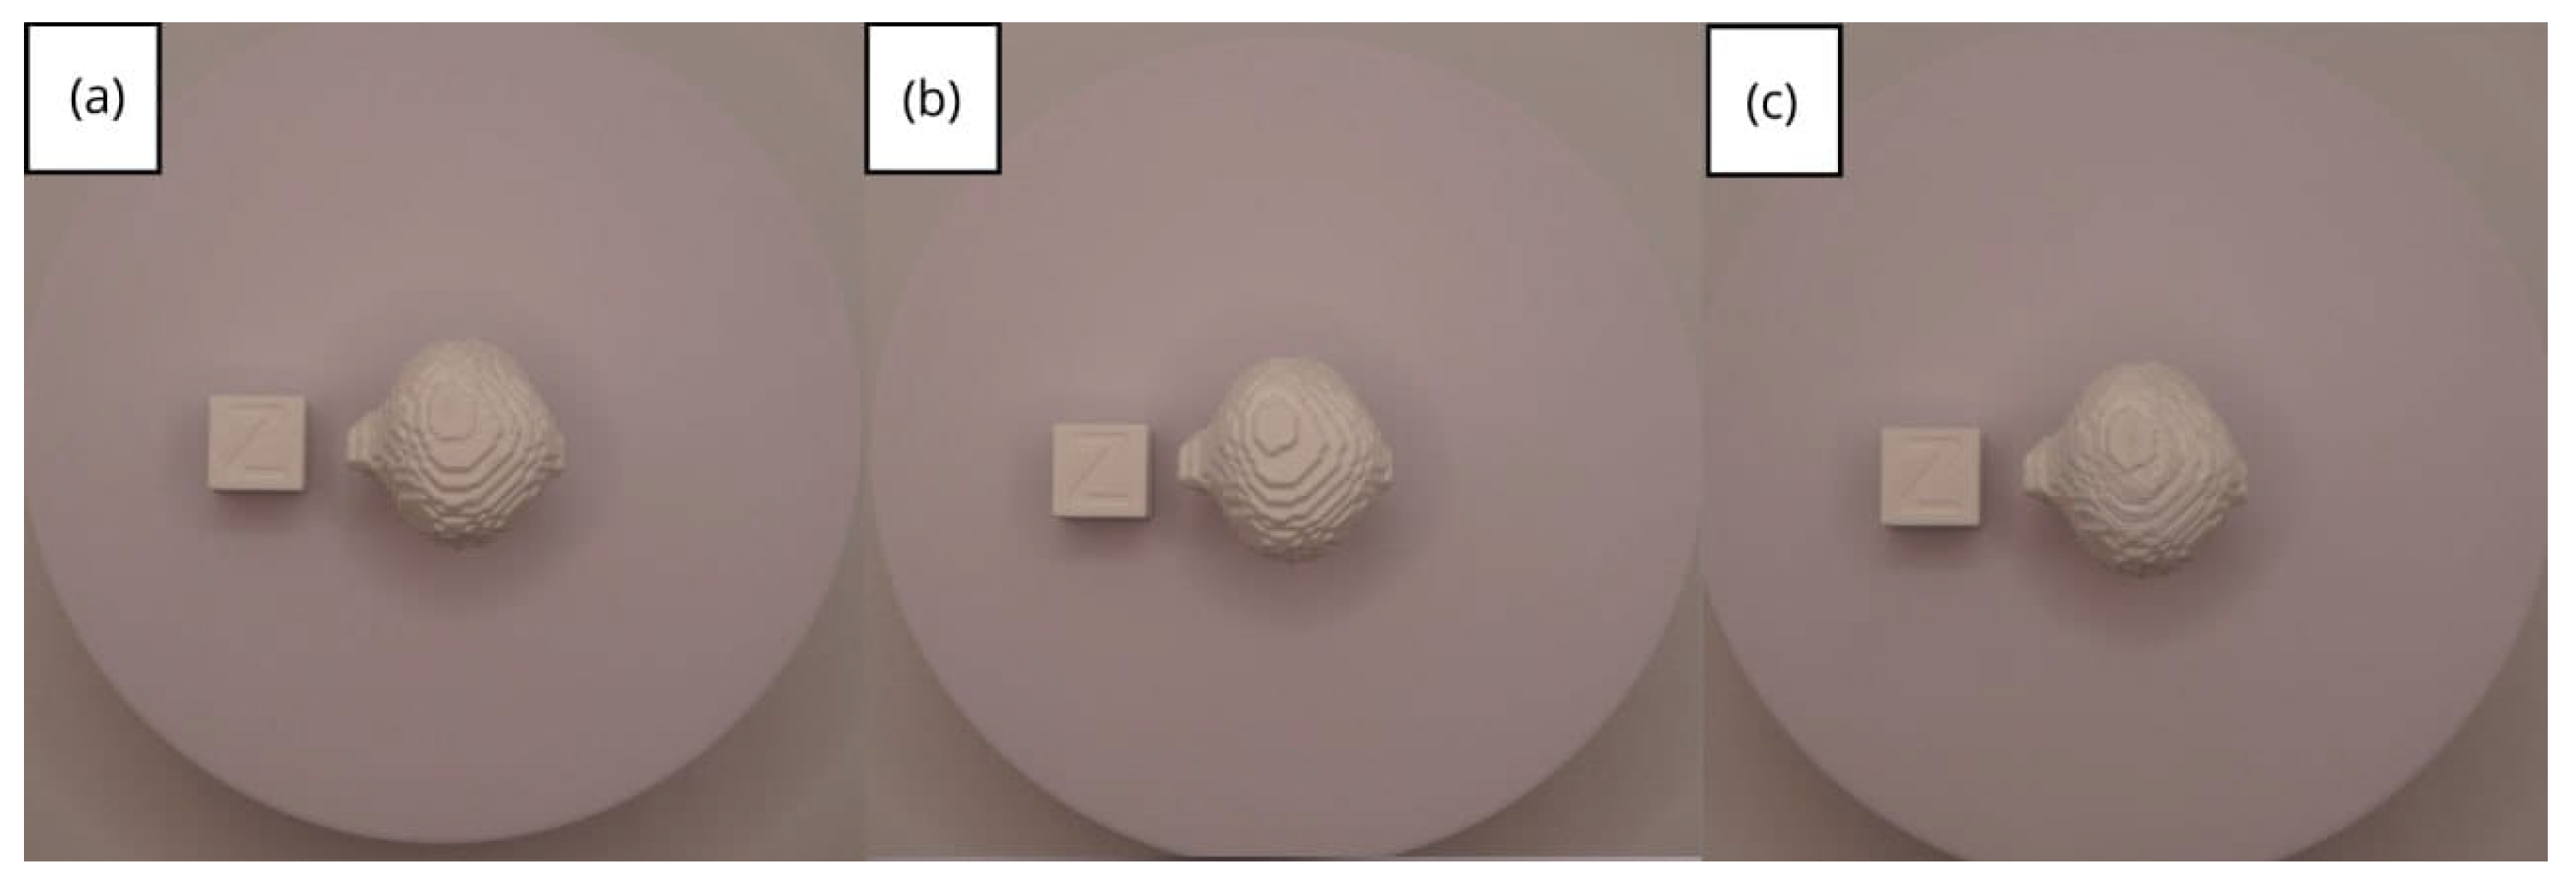

3.1.3. Final Printing

3.2. Human Lower Jaw

3.2.3. Final Printing

3.3. Human Brain Tumour

3.3.3. Final Printing

- Resolution loss: We can see in our protocol how the conversion process can lead to a reduction in image resolution, which could affect the fidelity of the 3D models. It is important to consider defining strategies in the DICOM file acquisition process to mitigate this resolution loss problem, such as optimising imaging parameters and carefully selecting segmentation thresholds. These losses are primarily dependent on the imaging process and are, therefore, beyond our control and the development of this protocol.